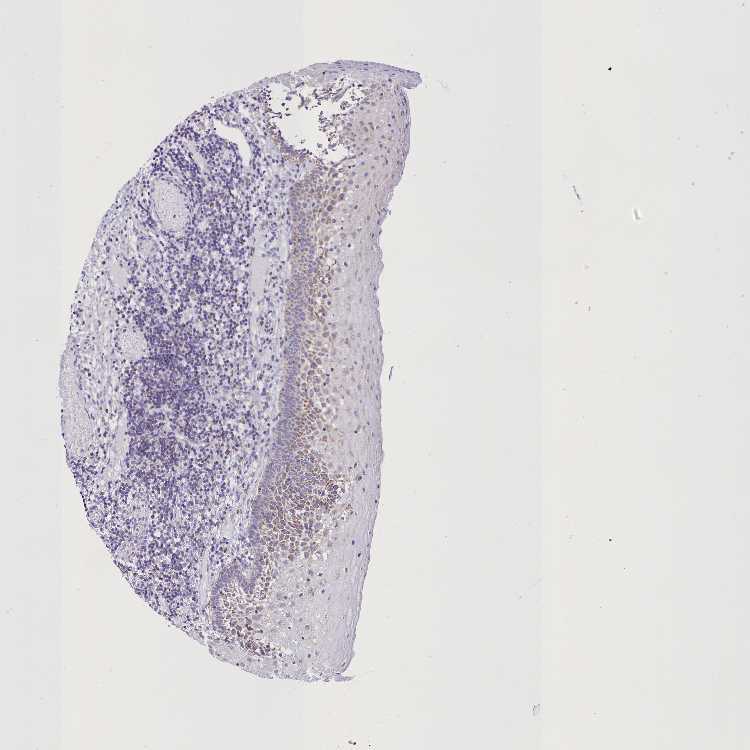

WDFY3